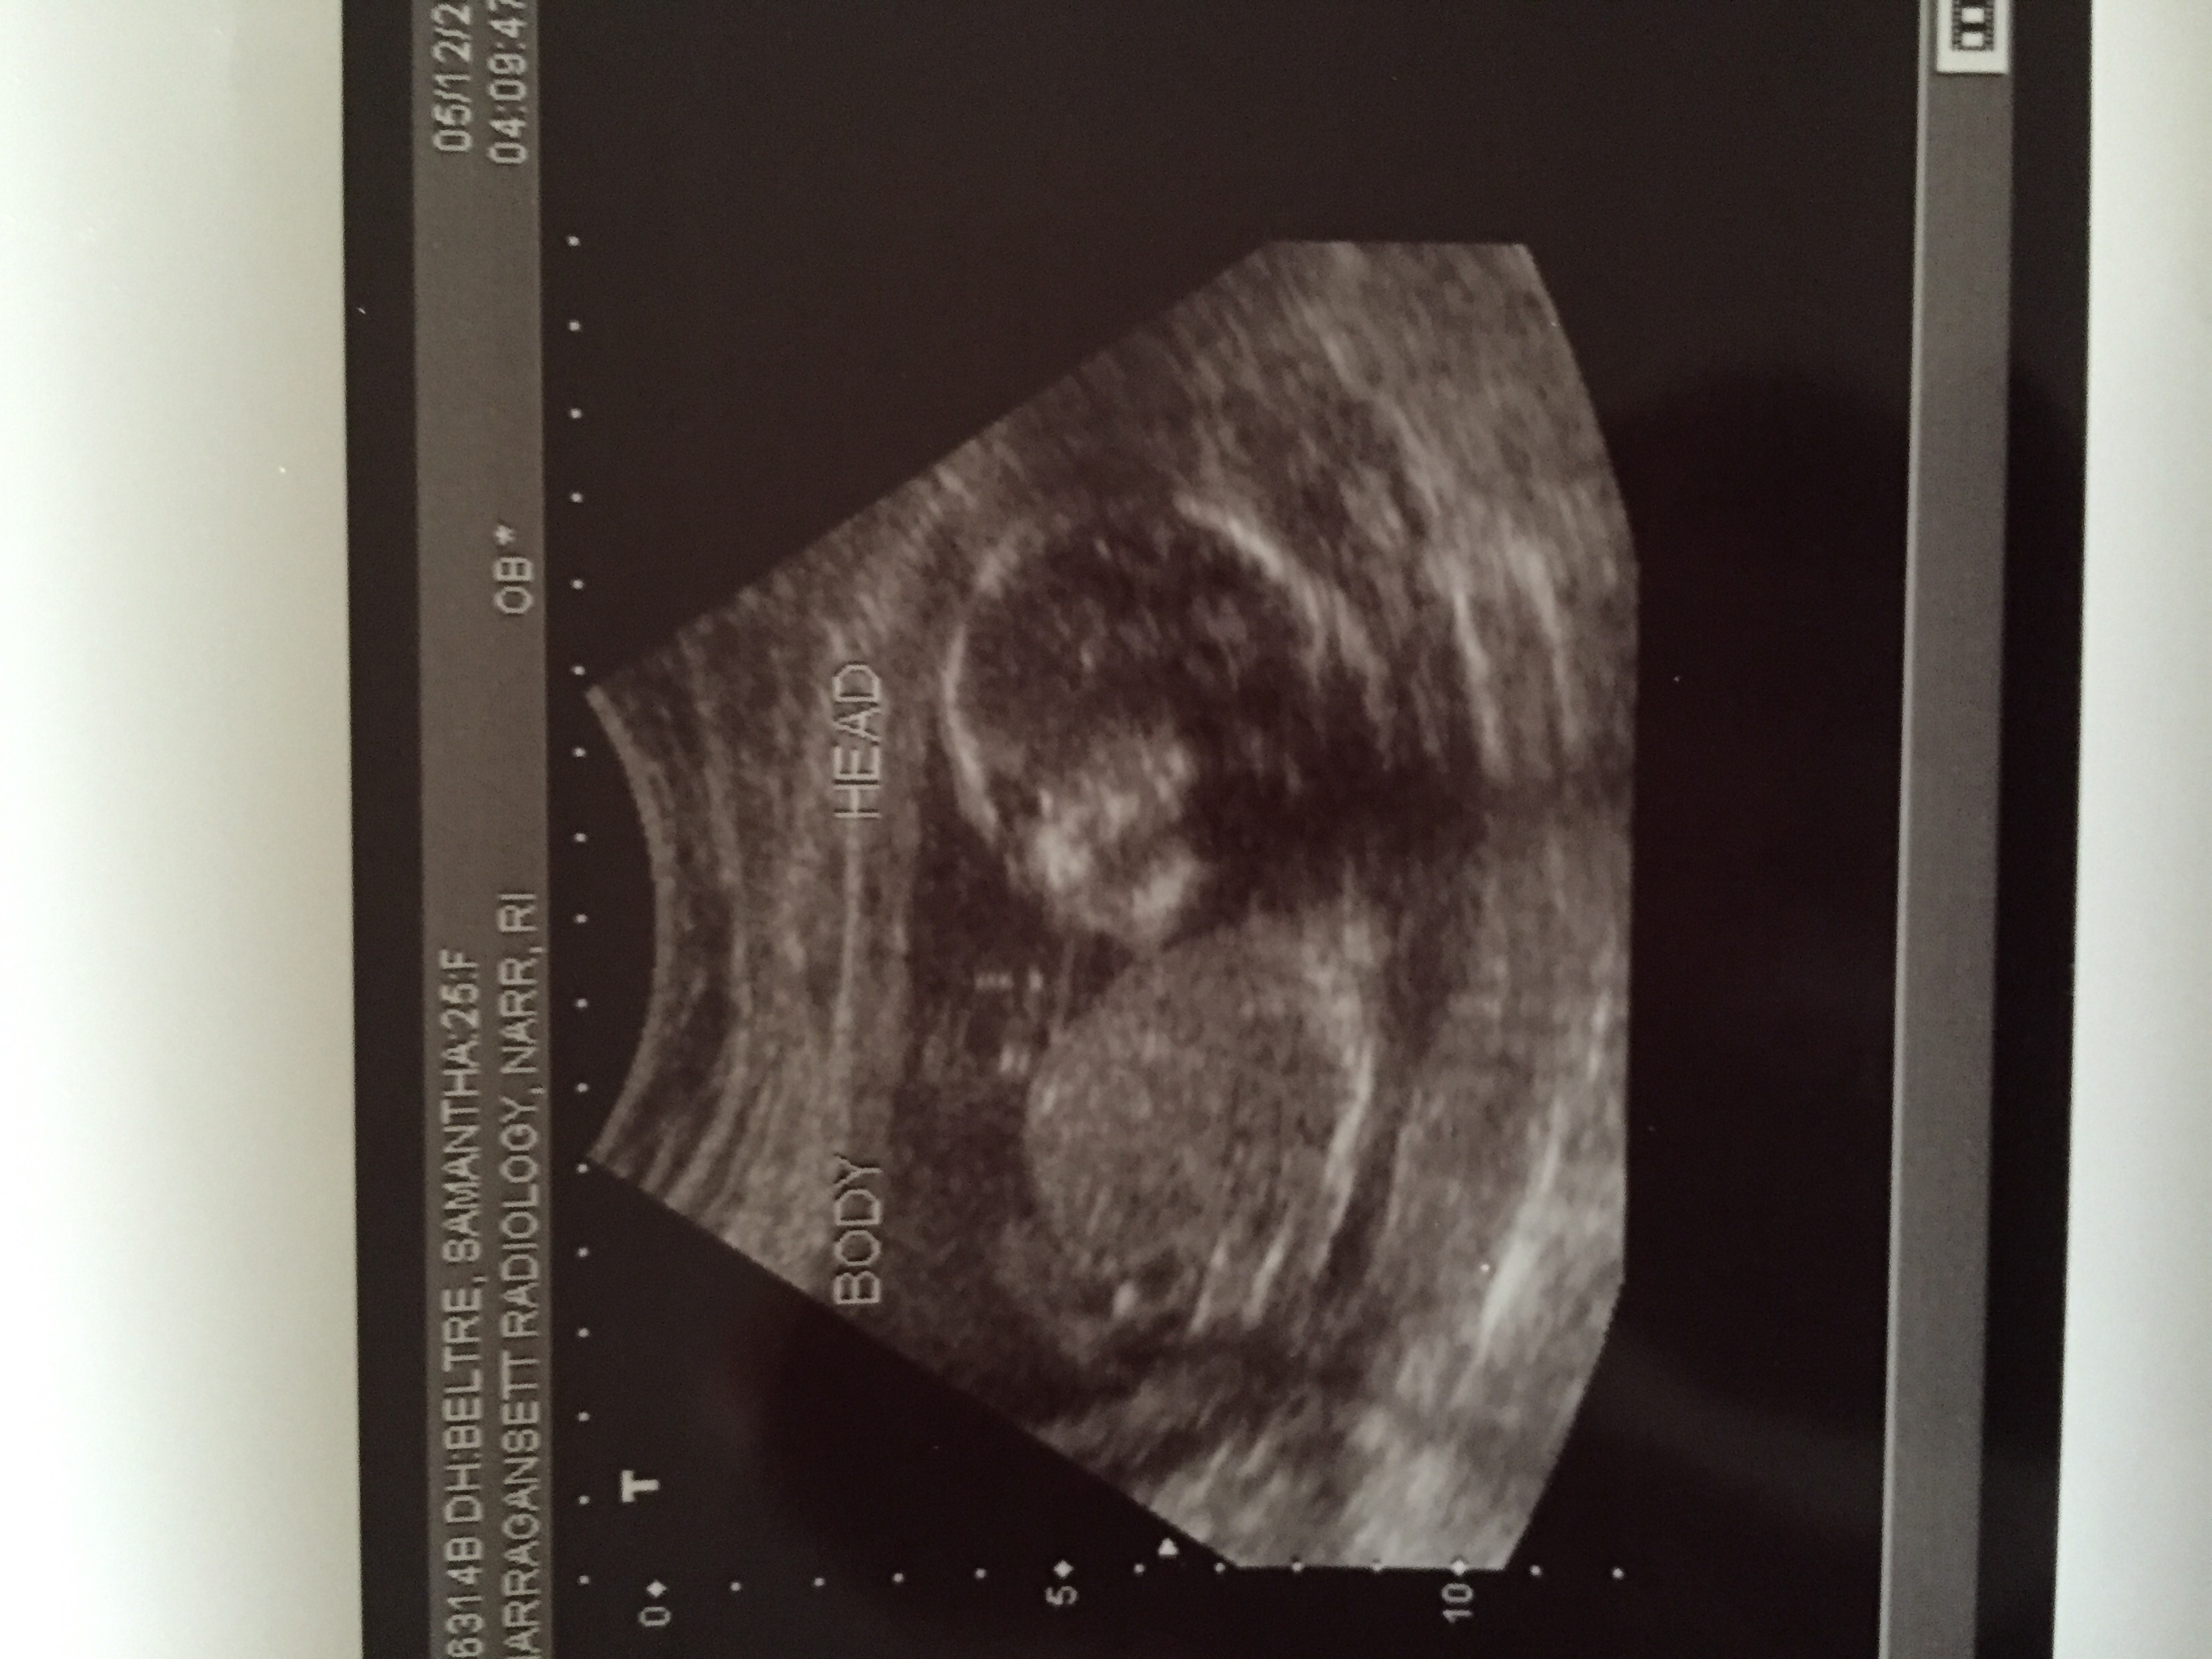

18 week ultrasound!

They confirmed he's still a boy!

The tech said he's measuring 81st percentile!!!

And everything looks normal! Coudnt be happier